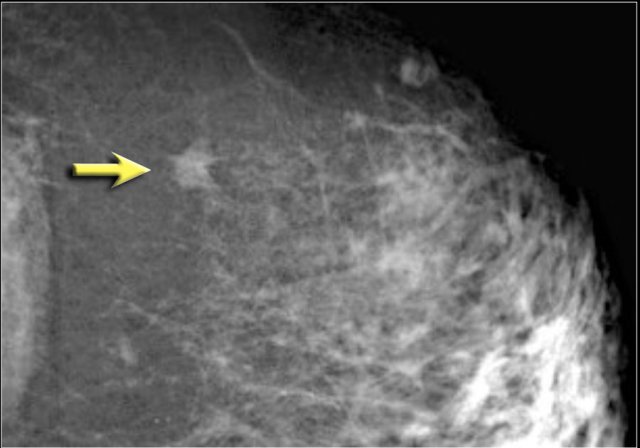

The upper image shows a few amorphous calcifications initially classified as BI-RADS 3.

At 12 month follow up more than five calcifications were noted in a group.

The findings were now classified as BI-RADS 4.

This proved to be DCIS with invasive carcinoma.